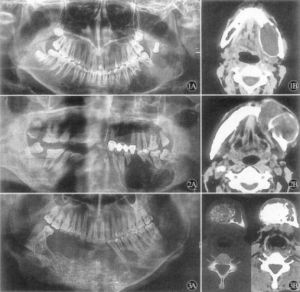

CT檢查1、X線檢查:X線攝片示頜骨膨隆,不規則多房性囊性透光影像,此影像邊緣不光滑,有半月狀切跡,分房大小懸殊,波及牙槽骨者可有明顯的“根尖浸潤征”--牙根尖的牙槽突骨質呈不規則的破壞與吸收,牙根可呈鋸齒狀或截斷樣吸收,如有迅速長大同時伴疼痛潰瘍等症狀,X線表現骨間隔破壞消失,呈斑點狀影時,應疑有惡性變。

高分辨螺鏇CT配合牙科軟體技術,特別是多層螺鏇CT的容積數據採集技術,不僅能夠重組出反映頜骨解剖特點的二維曲面圖像和任意方位上的二維圖像,而且能夠精細顯示病變的三維結構;由於CT有較高的密度解析度,還可顯示病變的內部結構和囊內容物的密度;此外,套用不同的窗技術,還可分別觀察骨,軟組織病變的細節,所有這些改善均有助於頜骨造釉細胞瘤特徵的顯示。

4.X線攝片示頜骨膨隆,不規則多房性囊性透光影像,此影像邊緣不光滑,有半月狀切跡,分房大小懸殊,波及牙槽骨者可有明顯的“根尖浸潤征”--牙根尖的牙槽突骨質呈不規則的破壞與吸收,牙根可呈鋸齒狀或截斷樣吸收。

5.如有迅速長大同時伴疼痛潰瘍等症狀,X線表現骨間隔破壞消失,呈斑點狀影時,應疑有惡性變。